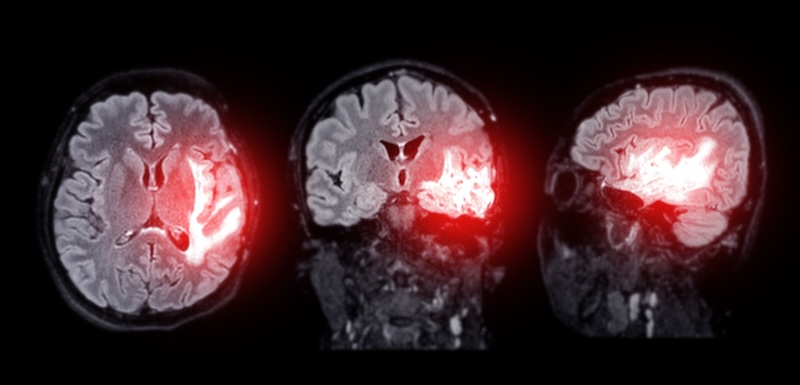

Scientists find a new way to treat Alzheimer’s disease

Scientists at Nanyang Technological University in Singapore have made an important discovery that could lead to new treatments for Alzheimer’s disease, the most common form of dementia. They found a key “energy switch” in immune cells called microglia, which are vital for brain health. These cells help clear toxic proteins that build up in the […]